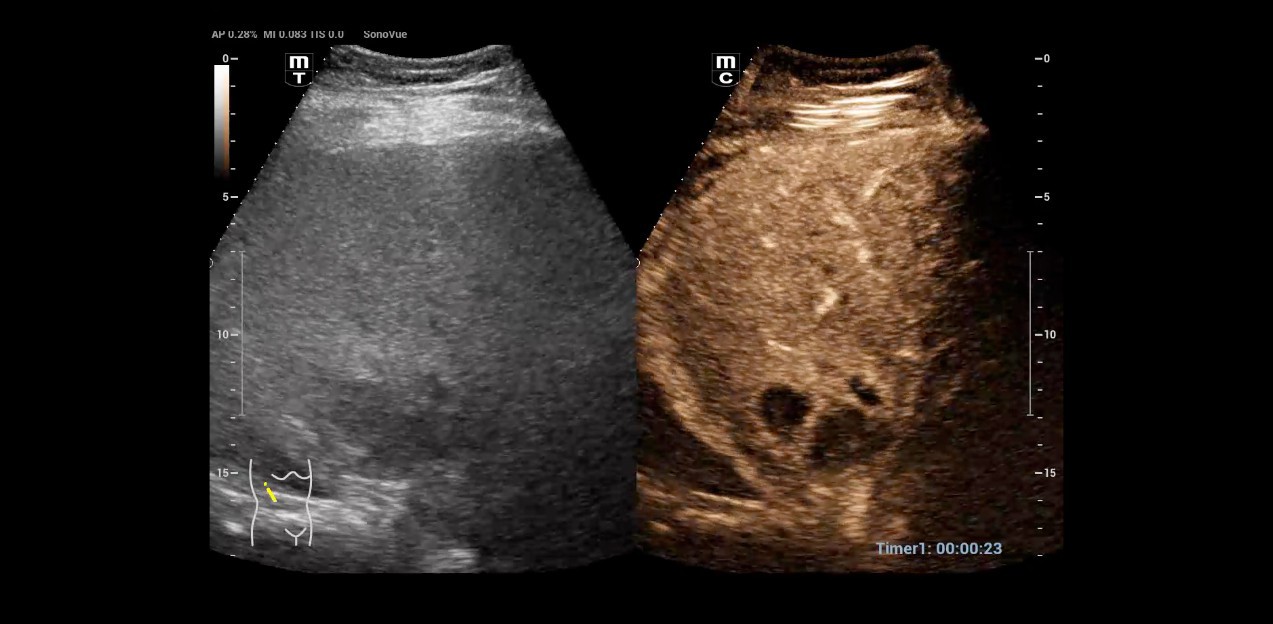

1. Contrast agent sonography in case of uncertain liver lesion shows a liver abscess. The questionable area showed no perfusion.

Dr. Seibel chose Resona I9 for various reasons. First, the high-end device offers excellent image quality with high resolution, as well as focused examination techniques that facilitate diagnosis. For instance, he frequently uses contrast-enhanced ultrasound (CEUS) to clarify uncertain findings.

I just examined a patient whose heart was not visible in the original image. Therefore, I used contrast media to assess the heart function better. Additionally, this patient had an unusual structure on the lung surface that raised the question: Is there no blood flow or is the area still perfused? CEUS can also address this issue. These are two distinct studies, and being able to conduct both on one system is significant.